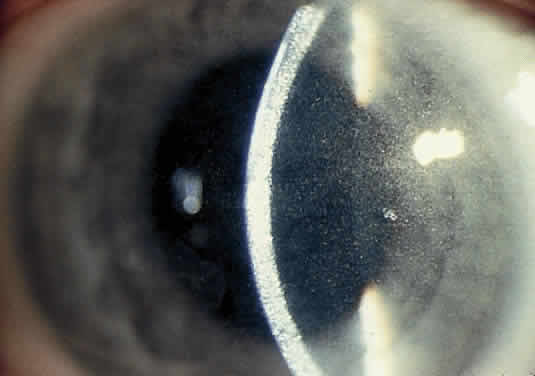

OCULAR FINDINGS. The outstanding clinical feature common to all three phenotypes is the corneal and conjunctival cystine crystal deposition (Figs. 3 and 4). Photophobia is often the only presenting visual symptom; this may be incapacitating and associated with blepharospasm.

Corneal deposits appear as a layer of homogeneously distributed, fusiform or needle-shaped, iridescent crystals situated in the stroma beneath the epithelium. In the infantile form, anterior crystal deposition begins early in life (between 6 and 15 months of age) and proceeds posteriorly as the patient ages; deposition advances more rapidly in the periphery. The anterior location of the crystals may be associated with recurrent erosions.33 The depth of the stromal deposition and the density of crystals is always greater peripherally than centrally. More and larger crystals occur in the superficial stroma. No visual impairment occurs at this early stage. By the age of 7 years, most patients have crystals, either within or on the endothelial surface34,35; markedly decreased corneal sensitivity is also present.36 The spherical contrast sensitivity function is significantly lower in infantile cystinosis than in age-matched controls.37

The conjunctiva has a ground-glass appearance. Polychromatic, polymorphic, rectangular, or rhomboidal crystals can be seen with the biomicroscope.